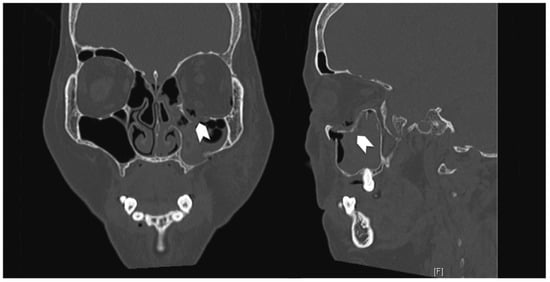

A 66-year-old woman sustained a left ZMC fracture and orbital floor fracture following a fall (Figure 5), resulting in left enophthalmos and diplopia on upward gaze. She underwent ORIF and orbital floor reconstruction 12 days after the injury. Both the 0.4-mm titanium orbital mesh and orbital rim plate were used (Figure 6). Postoperatively, she complained of progressive worsening of left upward gaze diplopia, starting around 2 weeks postoperatively and worsening over 4 weeks. There was also dimpling noted over the left lower lid due to lid retraction; however, forced-duction test was negative. She was given lower eyelid scar massage, which was performed in an upward oblique fashion from medial to lateral, and steroid injections (8 IU of triamcinolone) into the lower eyelid. On the 9th week postoperative follow-up, she reported improvement of diplopia but still had lower eyelid retraction and a tugging sensation (Figure 7). She was then given 0.3 mL of hyaluronic acid (HA) filler (Restylane; Galderma, Lausanne, Switzerland) into the posterior lamella space to correct the lower eyelid retraction. She experienced immediate and sustained (at 1 month) relief of symptoms of tugging and eyelid retraction.

Figure 6. Coronal and sagittal cuts of the postoperative CT scan of the face (Case 2) demonstrating reduction of all periorbita. Although the posterior edge of the plate is slightly depressed, there is no tethering of the inferior rectus muscle.